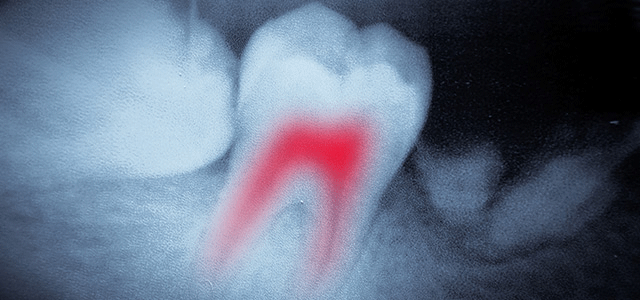

Dental XRays Are They Safe and Necessary

Dentists and hygienists are often asked about the safety and necessity of X-rays. This is a great question - with answers that differ from patient to patient. So let's examine it a bit further. You may be surprised to learn just